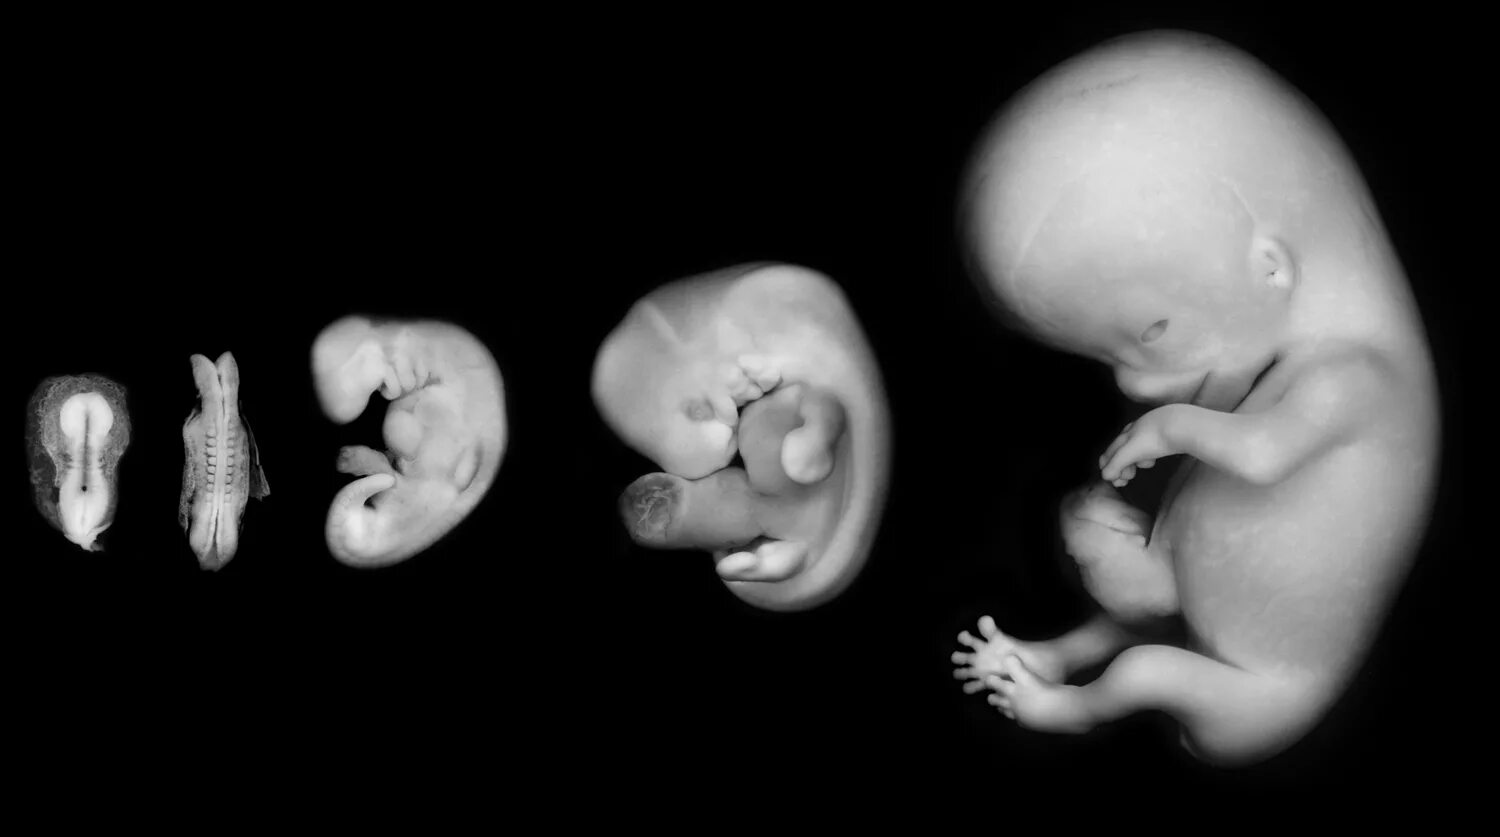

Куда девается эмбрион